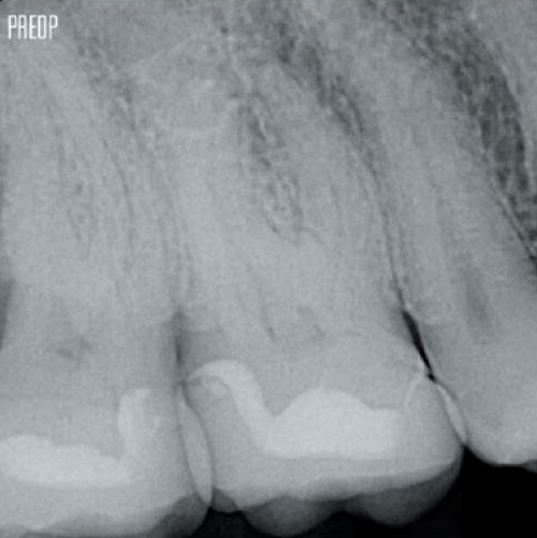

Un tratamiento exitoso de conducto radicular comienza con un acceso adecuado a la cámara pulpar. El procedimiento ideal proporciona acceso a la entrada del conducto radicular con una pérdida mínima de dentina.

Se recomienda utilizar una cavidad endodóntica conservadora (Conservative Endodontic Cavity, CEC) con el sistema TruNatomy®.

Ahora el acceso es posible desde diferentes ángulos mientras que, anteriormente, había que sacrificar la estructura (cavidad endodóntica tradicional).1

No es necesario el acceso en línea recta.1

La unión de la geometría de la lima, la conicidad regresiva y el alambre delgado y altamente flexible permite un tratamiento eficiente del conducto radicular y, al mismo tiempo, elimina solo la dentina cuando es clínicamente necesario.1

Fotos cortesía del Dr. Ahmed Salman